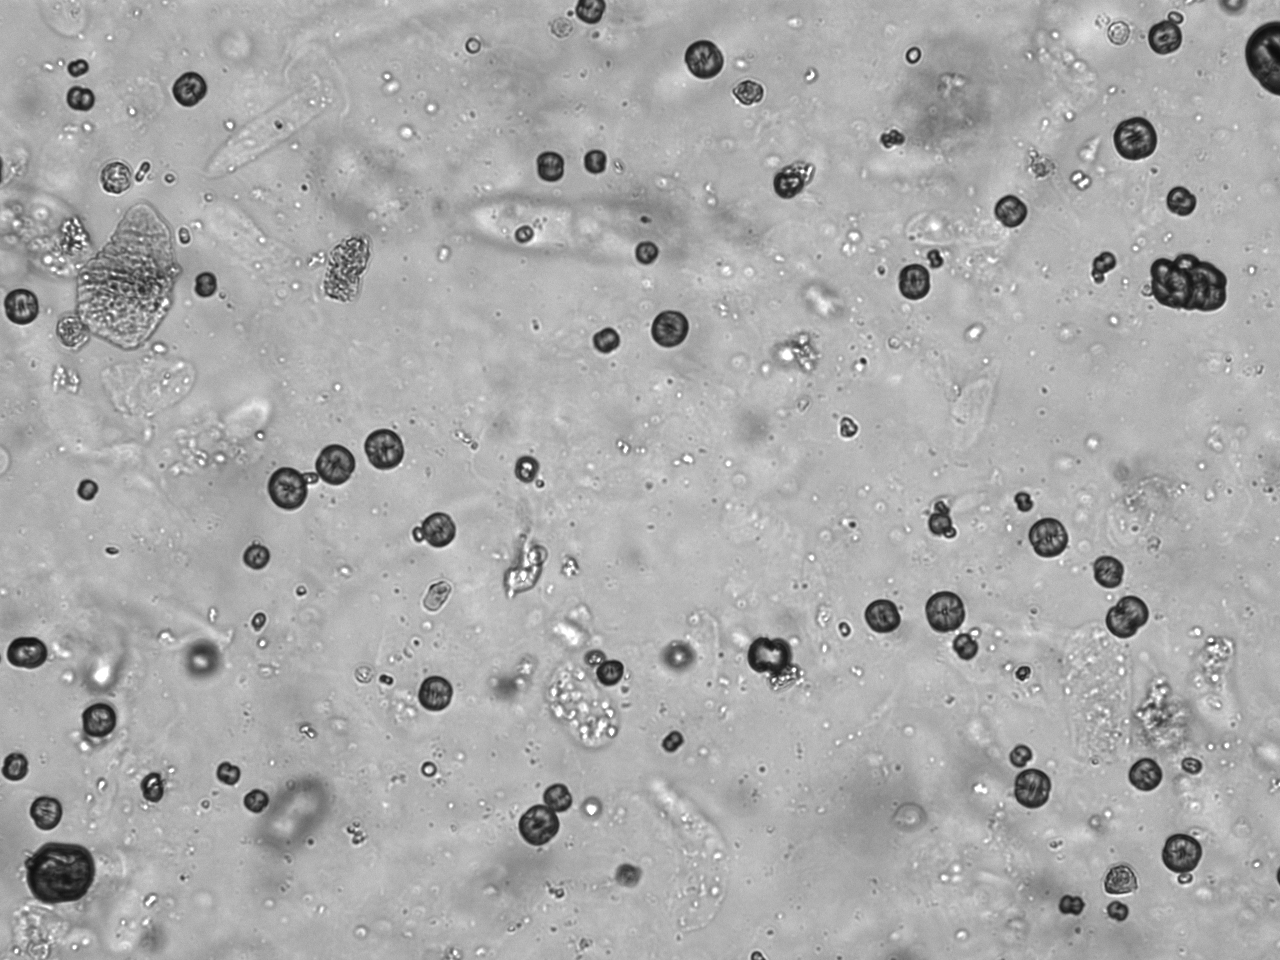

Urin-Feature: Leucinkugeln